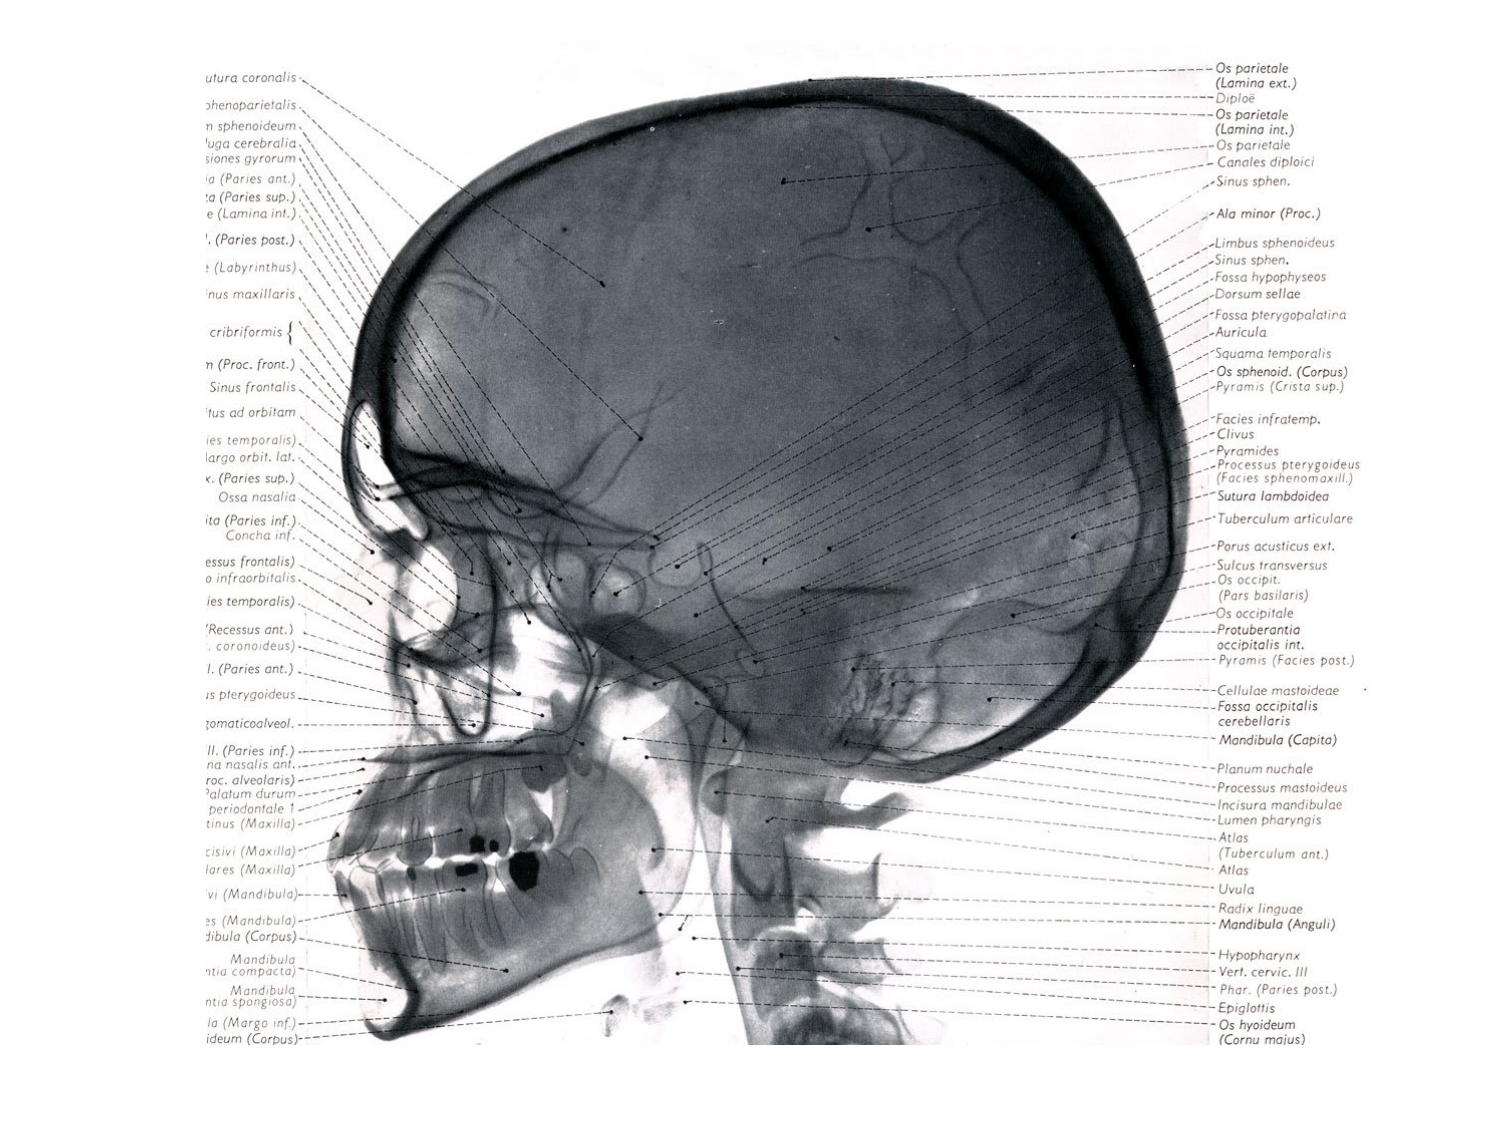

Anatomie du système endocrinien2

Bases de l'anatomie · 92 pages · 12 sections